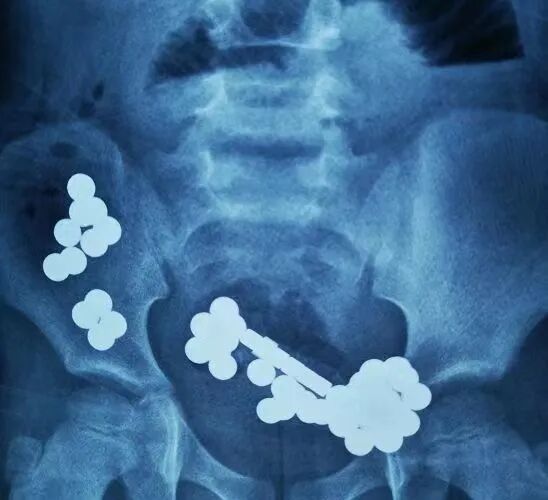

5. 磁性异物:磁珠、磁铁等;其中其中尖锐异物、纽扣电池、多枚磁性异物或单枚磁性异物合并金属异物发生并发症的风险较高,危险性较大。

- 误食多枚磁珠可致胃肠穿孔 -